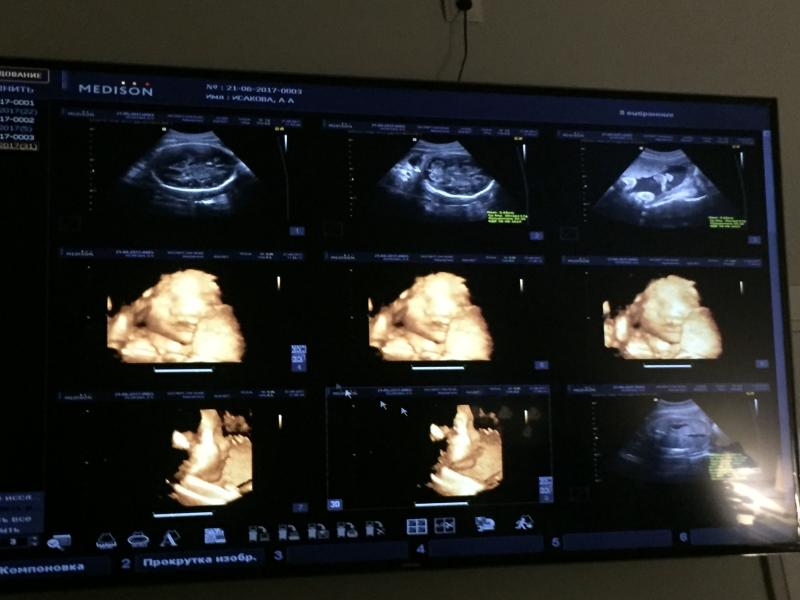

Сегодня съездили загород. Немного тянул и болел низ живота. Но быстро прошло. Третий день уже в квартире все мою, сегодня вымыла все окна. Но очень раздражаюсь все равно от каждой пылинки. Хочется, чтобы все было чисто к нашему возвращению домой. Малыш пинается, икает🐣спрашиваю у него "когда к нам выйдешь?", но он не хочет...обвиняю мужа..."он не хочет к папе😂"скорее всего он в меня...я тоже не хотела выходить, мама родила меня переношенной на две недели почти🤰🏻интересно, на кого он будет похож...по 3Д узи похож больше на мужа, но мой греческий нос кажись у него есть🤦🏻♀️